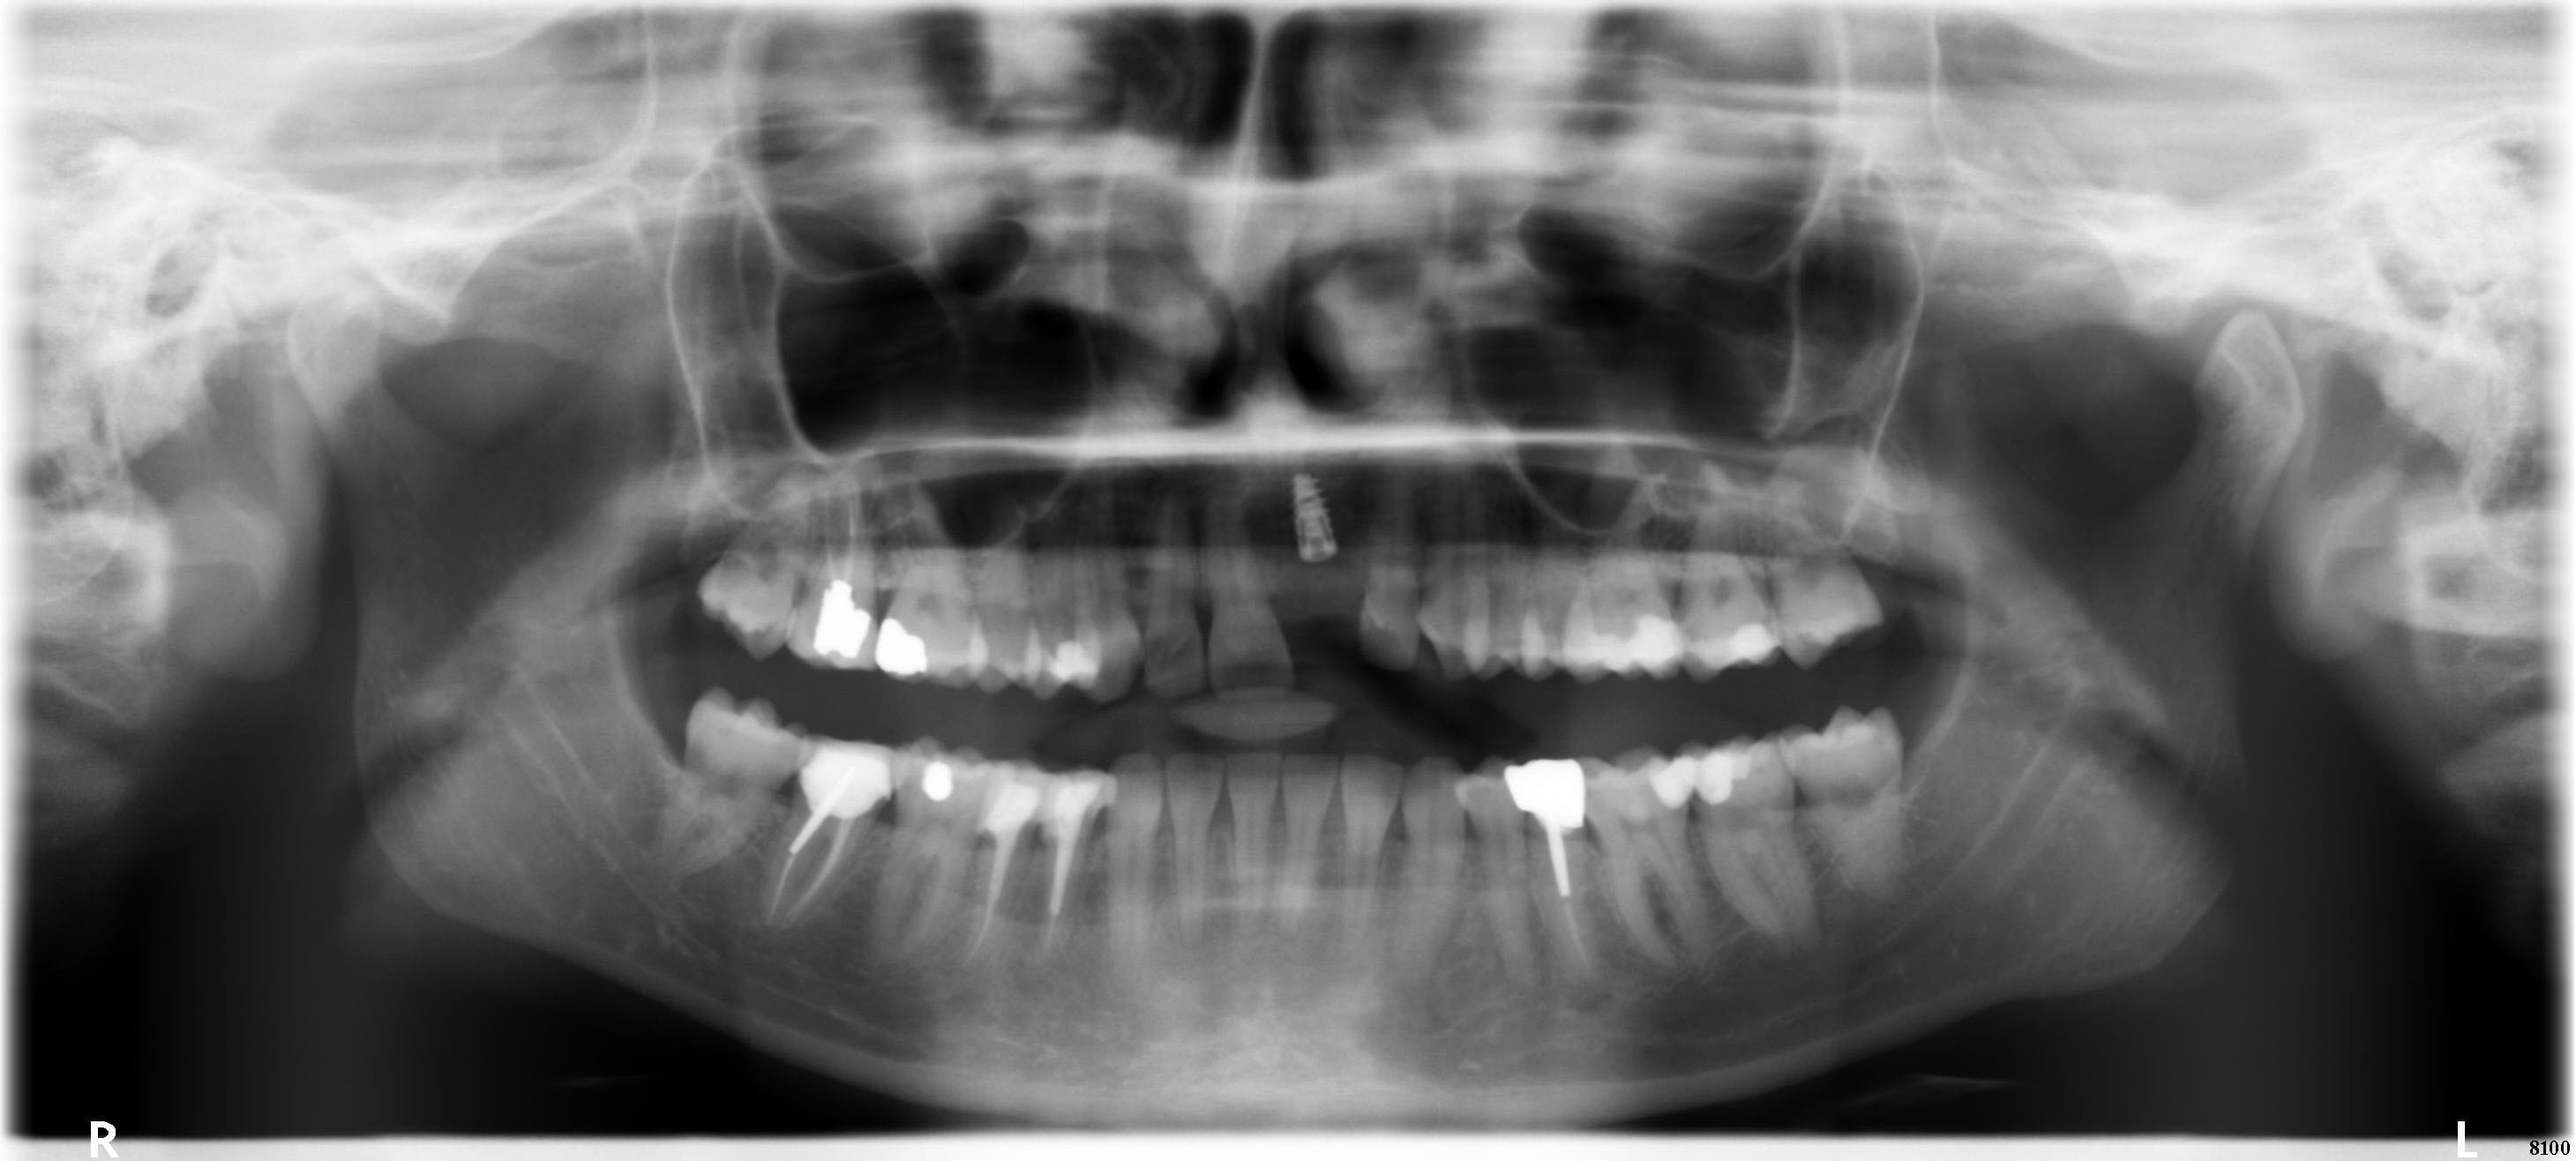

Voici pour la panoramique à 6 jours post op.

Les sinus paraissent clairs.

J'ai pensé aussi à un effet secondaire de l'antibiotique... Elle le terminait hier soir, donc si c'est ça amélioration à prévoir aujourd'hui et demain, je serai vite fixé. Mais j'y crois moyen...

Anti inflammatoires, il y a eu 3 jours d'Ibuprofene 400mg x3/j après l'intervention, et le médecin traitant consulté a rajouté 2 jours de cortisone ensuite. Fini depuis 2 jours. Aucune variation dans les symptômes.

Pano uiihvz - Eugenol

Euh... ton implant est très très enfoui esthétiquement je pense que ça va pas être une super surprise (même si elle recouvre, pense que les patients regardent toujours en soulevant la lèvre...) ensuite par rapport à l'apex de ta 11 il semble très haut, je ferai une 3D perso pour voir mon plancher des fosses nasales.